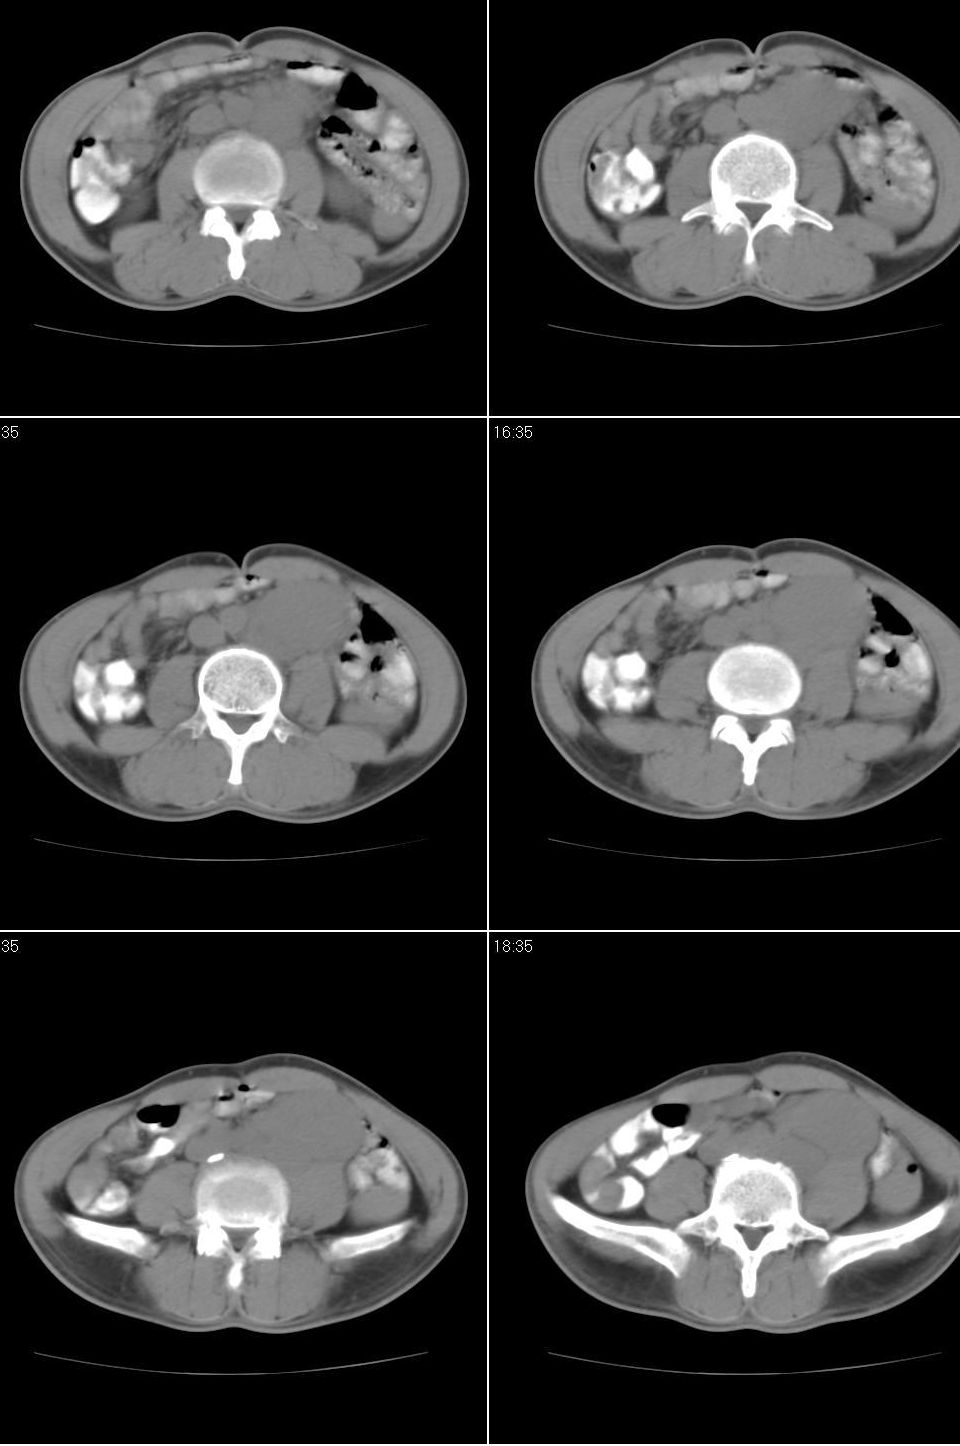

以下是引用jiangjing在2007-9-18 17:20:00的发言:[br]考虑生殖细胞肿瘤伴腹腔及腹膜后与腹股沟区淋巴转移,腹膜后大血管受压受侵

以下是引用老爱克斯新网客在2007-9-18 18:27:00的发言:[br]主动脉旁左侧腹股沟可见多发结节状病灶,1淋巴瘤,2转移瘤待除外,